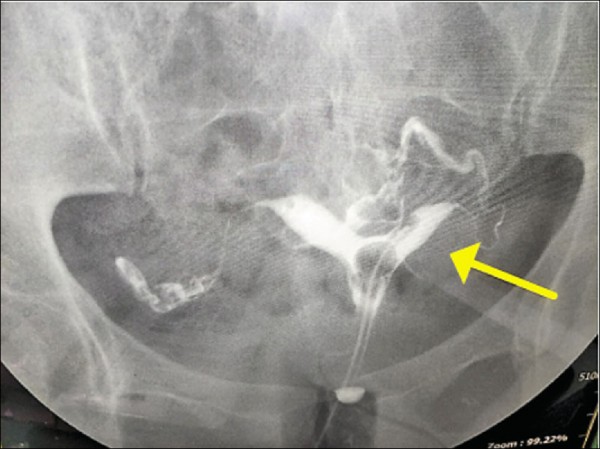

童綜合醫院不孕科醫師張永玲指出,所謂「雙角」是胚胎發育時,苗勒管形成子宮但未熔斷,子宮的尾部正常,但頭部分叉,子宮呈現「心型」,整體看起來像是愛心,因此又稱「心型子宮」。

雙角子宮患者的月經量常過多且經期過長,但可以懷孕,一般不用處理,不過因子宮內膜為胚胎成長發育的位置,若習慣性流產者或長時間未懷孕可考慮手術治療。